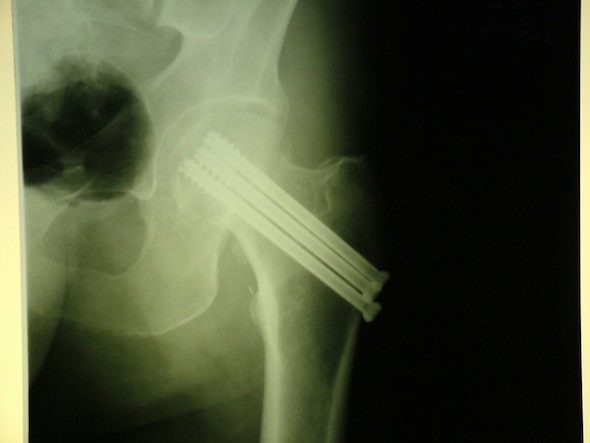

- Винты и пластинки. Вначале производится репозиция перелома — установка на прежние места костных отломков. Поврежденные фрагменты фиксируются специальными шурупами, а также пластинками, которые крепятся на внешних костных поверхностях.

- Остеосинтез. Мы уже рассматривали его в предыдущем разделе. Стержень выступает своеобразной осью, на которую нанизывается сама бедренная кость и все ее осколки.

Остеосинтез бедренной кости Термином остеосинтез бедра называют хирургическую операцию в травматологии, при которой проводится максимально точное сопоставление поврежденных фрагментов бедренной кости, в последующем их жестко фиксируют специальными устройствами для сращивания.

Какие виды остеосинтеза существуют?

Интрамедуллярная, когда крепежная спица или шифт устанавливается в спинномозговой канал, накостная, когда пластины крепятся к кости снаружи, чрескостная, когда крепеж охватывает кость в месте перелома, пересадка костной ткани, когда в качестве фиксатора используется кость пациента.